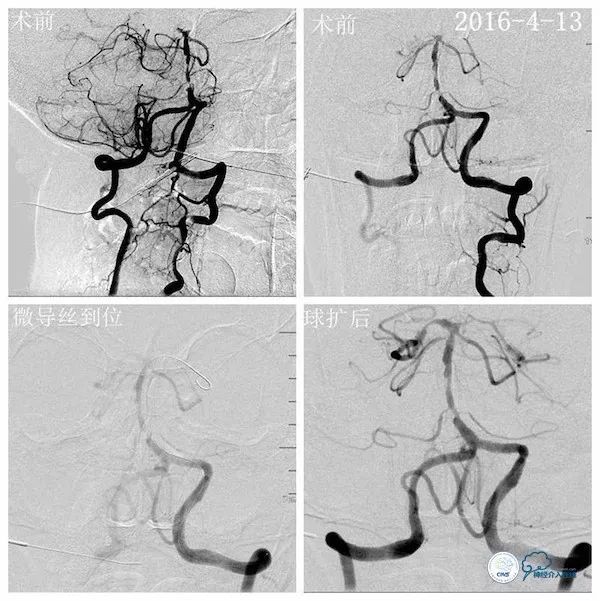

行头颅DSA示左椎动脉优势,左椎动脉V2段迂曲,基底动脉下段重度狭窄;左颈动脉造影见左后交通动脉开放,向双侧大脑后动脉及基底动脉远段代偿(2016-4-11,图3、4、5)。

图3

图4

图5

考虑到基底动脉下段重度狭窄,斑块波及范围虽然较长,但最重处较为局限,故选择Gateway2.0×9mm球囊对狭窄最重处予以扩张,扩张后造影示残余狭窄约30%(2016-4-13,图7)。

图7